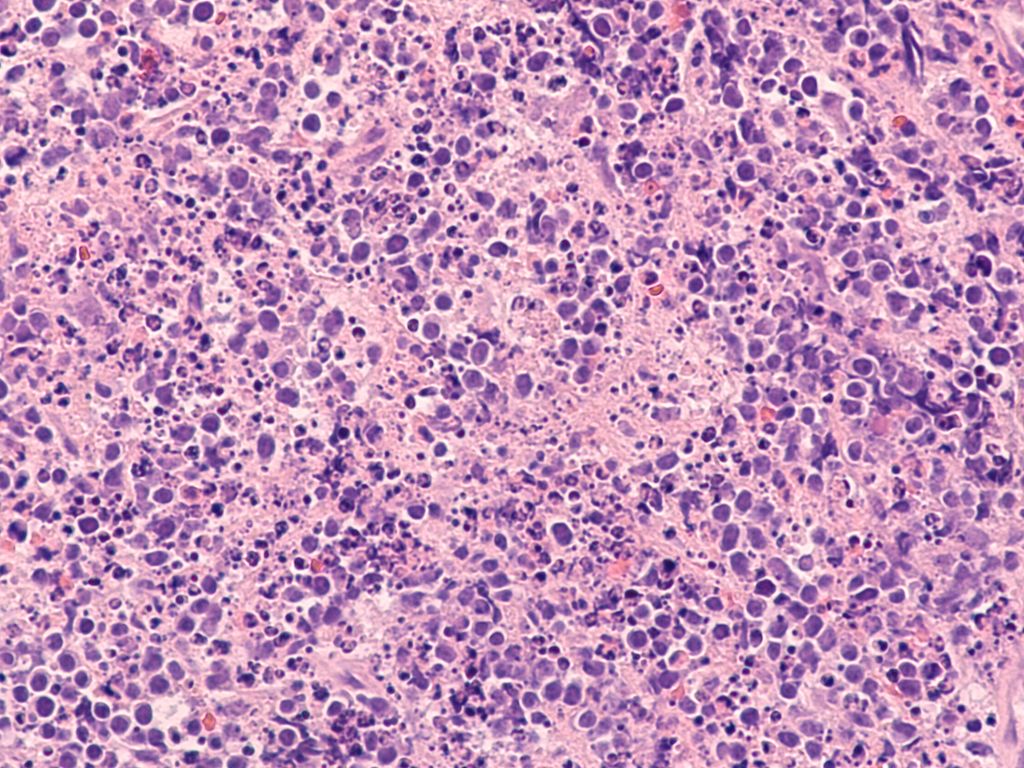

Diffuses großzelliges B-Zell-Lymphom (DLBCL)